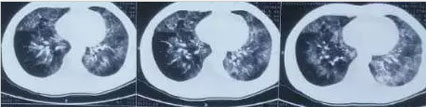

患者胸部CT表现